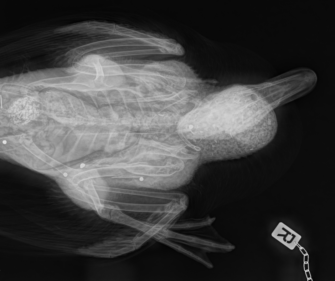

Am 19. Oktober wurde auf dem Truppenübungsplatz Altmark ein Deutscher Jagdterrier getötet. Wie genau es dazu kam untersucht nun das Leibniz-Institut für..